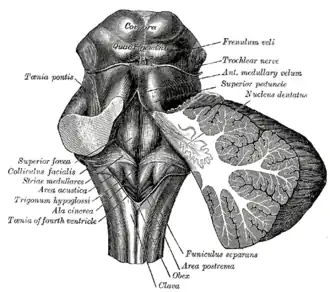

Ромбовидная ямка.

Ромбовидная ямка. Срединный сагиттальный срез головного мозга.